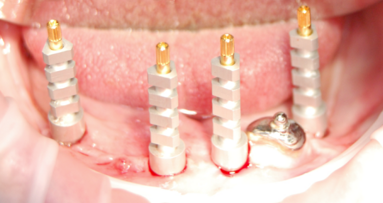

Zabieg wykonano w znieczuleniu miejscowym 4% chlorowodorkiem artykainy z dodatkiem noradrenaliny. Usunięto wszystkie zęby i korzenie oraz wyłuszczono z okolicy 34-35 zmianę makroskopowo mającą wygląd torbieli korzeniowej, co potwierdzono w badaniu histopatologicznym. Następnie, po przecięciu i odwarstwieniu błony śluzowej wraz z okostną, wykonano preparację kości części zębodołowej żuchwy w pozycjach 33 i 43. W prowadzono wszczepy o Ø 4,0 mm i długości 14 mm w okolicy 33 oraz Ø 3,5 mm i długości 14 mm w pozycji 43. Rany zszyto szwami pojedynczymi nylon 5-0. Po zabiegu zalecono doustną antybiotykoterapię z amoksycylliny w dawce 2 g na dobę, w 2 dawkach podzielonych przez 7 dni. W celu zmniejszenia dyskomfortu pooperacyjnego, stosowano nimesulid w dawce 0,1 g doustnie 2 razy na dobę. Gojenie przebiegało bez powikłań, szwy usunięto w 7. dobie. Odciążono płytę protezy w miejscach położenia implantów oraz nieznacznie zwiększono jej zasięg w wymiarze przedsionkowym i językowym celem poprawy retencji.

Przyjęto 12-tygodniowy protokół gojenia zamkniętego. W tym czasie wykonano 3 wizyty kontrolne w odstępach 4-tygodniowych. Pierwsza wizyta nie wykazała żadnych nieprawidłowości w osteointegracji, pacjentka nie zgłaszała dolegliwości (Ryc. 2). Utrzymanie protezy górnej pacjentka określiła jako wystarczająco komfortowe, ale zgłaszała trudności w użytkowaniu protezy dolnej.

Kolejna kontrola została wykonana po następnych 4 tygodniach. Także i tym razem pacjentka nie zgłaszała bólu, jedynie dyskomfort w utrzymaniu dolnej protezy oraz utrudnione spożywanie posiłków. W badaniu wewnątrzustnym stwierdzono odleżynę po stronie językowej w okolicy 33. Ponadto, podczas palpacji tego fragmentu części zębodołowej, na granicy dziąsła i dna jamy ustnej stwierdzono miejsce poddające się uciskowi, który wywoływał niewielką tkliwość. W rtg pantomograficznym i TK stwierdzono w okolicy wierzchołka implantu 33 obecność ogniska lizy tkanki kostnej z uszkodzeniem blaszki językowej. Zmiany przypominały „zapalenie okołowierzchołkowe”. Ognisko powyższe osiągnęło rozmiar 6 mm w wymiarze przedsionkowo-językowym oraz 7 mm mezjalno-dystalnie. Blaszka kostna przedsionkowa nie została zniszczona, tkanka kostna przedsionkowo miała szerokość 4 mm w rzucie zapalenia. Co ciekawe, kość i tkanka miękka wokół szyjek implantów nie wykazywały żadnych zmian patologicznych (Ryc. 3-6).

Po kolejnych 4 tygodniach odsłonięto wszczepy i umocowano protezę całkowitą dolną na łącznikach typu „locator”. Na wizytę kontrolną pacjentka zgłosiła się po 2 tygodniach. W badaniu nie stwierdzono nieprawidłowości, retencja protezy została określona przez badaną jako bardzo dobra.